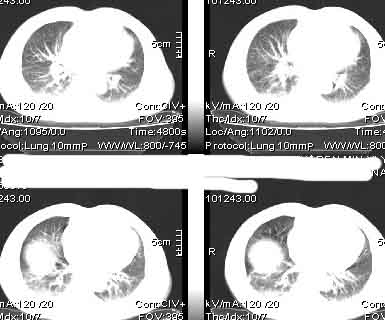

该病例我的诊断意见:右肺上叶周围型肺癌伴纵隔和右肺门淋巴结增大和右肺上叶阻塞性肺炎{病灶周围致密影以近肺门侧明显!}。右侧少量胸腔积液。

一. 1)症状有无发热及慢性过程.2)化验室检查?3)有无tb接触史?二.右肺上叶见片团状影,边界欠清,外侧方见一结节状软组织影,密度欠均匀,内可见低密度坏死区.周围强化明显,肺内见纤维索条影,局部胸膜增厚,但无明确胸膜凹陷.上叶支气管壁增厚,肺门及纵隔淋巴结增大.右侧胸腔少量积液.诊断意见:1右肺上叶慢性感染性疾病(肺tb?)伴肺门,纵隔淋巴结大.右胸少量积液.右肺上叶结节影多为tb球?2右肺上叶周围型肺ca伴肺门,纵隔淋巴结转移待排.右肺上叶炎变(肺门及纵隔淋巴结压迫).右胸少量积液.等待随返结果.

中轴间质增粗可以用癌局部淋巴侵润解释。近肺门侧片影用肺门淋巴结增大解释并压迫支气管引起近端炎症?